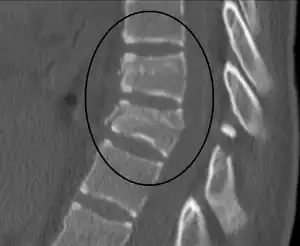

| Chance fracture | George Quentin Chance | horizontal fracture of vertebral body | hyperflexion of spine, seen in car accidents when lap belts were used | Chance fracture Archived 2018-07-06 at the Wayback Machine at Wheeless' Textbook of Orthopaedics online |